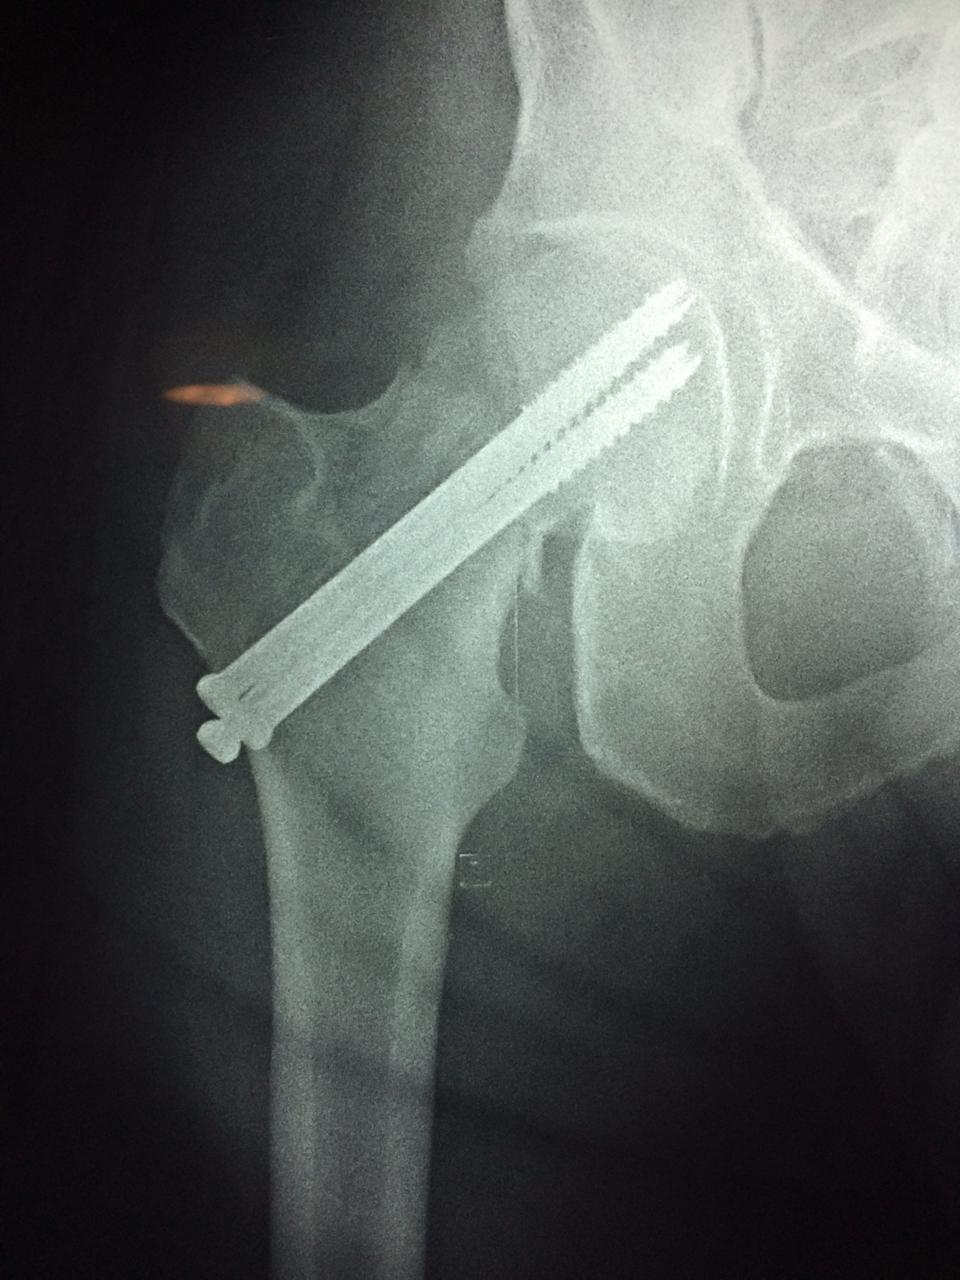

Cirugía de Fémur - Cadera

La cirugía de fractura de cadera se realiza para reparar una ruptura en la parte superior del hueso del muslo. Este hueso se denomina fémur.

Es parte de la articulación coxofemoral. Si una fractura de cadera no recibe tratamiento, es posible que deba permanecer en una silla o en la cama.